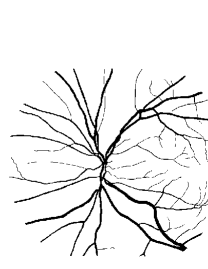

Refer to caption Refer to caption Refer to caption Refer to caption

(a)                                                                          (b)

(c)                                                                          (d)

Figure 9: Ground truth (left) and segmentation result (right): (a) and (b) are the images from DRIVE dataset, (c) and (d) are the images from the STARE dataset

V-B Vessel Segmentation Performance

The segmentation performance of the proposed model on three public available datasets is given in Table IV. It can be observed that the proposed model can achieve more than 95%percent9595\% segmentation accuracy on the DRIVE, STARE and CHASE_DB1 datasets, with the highest accuracy score Acc=96.0%𝐴𝑐𝑐percent96.0Acc=96.0\% achieved in the DRIVE dataset. Some exemplary segmentation results are shown in Fig.9. When treating the unknown regions as background regions, AUC=0.833 of trimap is 2.6%percent2.62.6\% lower than the proposed model while Acc of trimap is similar to the proposed model. In addition, Se=0.679𝑆𝑒0.679Se=0.679 of trimap is 5.7%percent5.75.7\% lower than the proposed model. These observations show that trimap can already have good segmentation performance, which indicates that the selection of region features is very effective in segmenting blood vessels. From Table IV, it can be observed that the model with vessel skeleton extraction can achieve more than 5%percent55\% increase of Sensitivity𝑆𝑒𝑛𝑠𝑖𝑡𝑖𝑣𝑖𝑡𝑦Sensitivity and 2%percent22\% increase of AUC𝐴𝑈𝐶AUC compared with the model without vessel skeleton extraction while Acc𝐴𝑐𝑐Acc of the model with vessel skeleton extraction is similar to the model without vessel skeleton extraction, which demonstrates the effectiveness of vessel skeleton extraction.